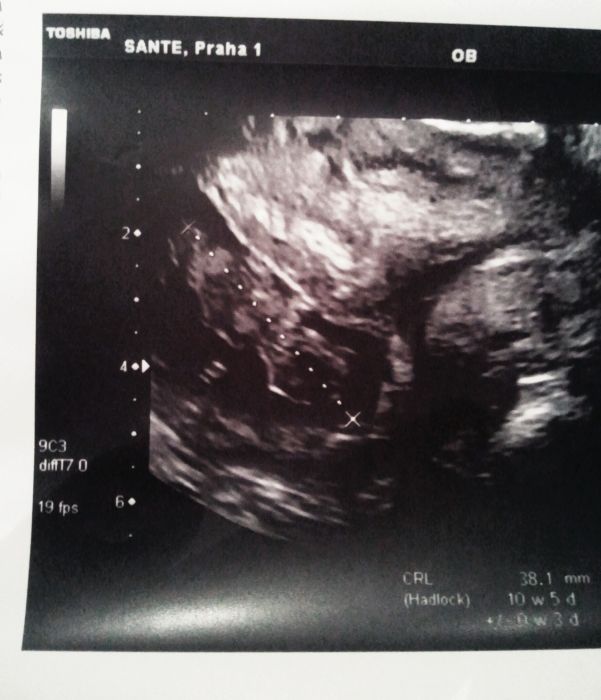

Ahoj holky, tak kontrola proběhla v pořádku, miminko roste jak má a jsem 10+5. Máme trochu lenocha, na fotku se ne a ne otočit na bok...jen se tam tak povalovalo